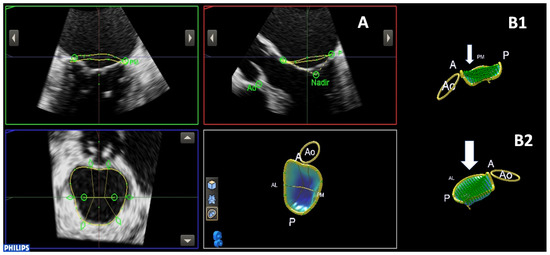

| Annulus ellipticity, % | 149 (112–170) | 162 (155–170) | 137 (112–160) | 0.048 |

| Tenting volume, mL | 4.7 ± 2 | 3.2 ± 1.2 | 6.3 ± 2.3 | 0.01 |

| Tenting height, mm | 8 ± 1.9 | 6.5 ± 1.4 | 9.6 ± 2.4 | 0.01 |

| MVQ analysis | 0.998 (0.993–0.999), p < 0.001 | 0.996 (0.988–0.999), p < 0.001 |